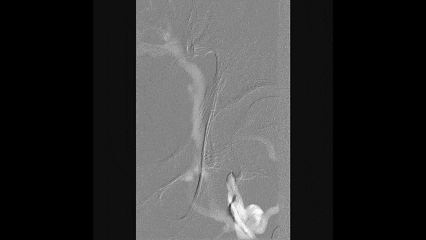

7

手术结果

术后造影显示:

左侧股深静脉到左侧髂外及髂总静脉全程通畅

侧支循环消失

形态良好,无明显狭窄,管腔通畅

临床效果:

术后患者左下肢肿胀明显减轻,溃疡疼痛缓解

术后3个月左下肢溃疡完全愈合